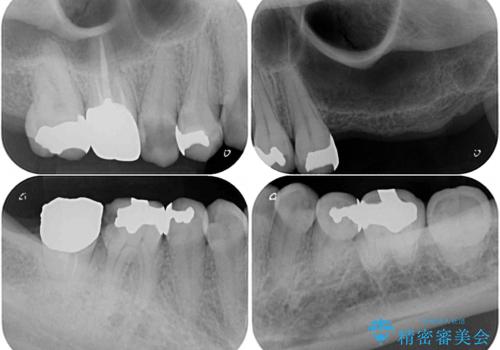

- 長年むし歯を放置してしまっているとのことで来院された患者様です。

神経が除去されている歯、根管治療の必要な歯、むし歯の非常に大きな歯に対してオールセラミッククラウンにて補綴治療を行うこととしました。

左上の欠損部はインプラントを埋入した上で補綴することとしました。

インプラント部は治癒待ちの期間が長くなるため、その期間を利用して下顎の叢生を解消し、より理想的な咬み合わせで補綴治療を行うこととしました。